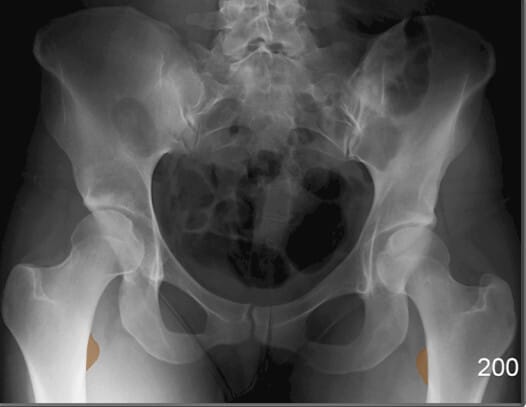

Bony Structures (AP View)

천골 (Sacrum)

| ✅ 요추 아래에 위치하며, 미골과 연결되는 큰 삼각형 구조입니다. AP view에서 정중앙 하부에 넓은 골 구조로 관찰됩니다. |

| 🔴 천장관절(sacroiliac joint)의 기준이 됩니다. |

미골 (Coccyx)

| ✅ 척추의 가장 하단에 위치한 작은 골절 구조로, 천골 아래에서 정중앙에 위치합니다. |

| 🔴 AP view에서는 짧고 좁은 골 구조로 보이며, 미골 통증(coccydynia)이나 외상 평가 시 주요하게 봐야 합니다. |

장골 (Ileum)

| ✅ 골반의 상부를 구성하는 큰 뼈로, 장골능(iliac crest)과 전상장골극(ASIS) 등을 포함합니다. |

| 🔴 AP view에서는 넓은 곡선형 음영으로 관찰되며, 골반 골절 여부 평가에 중요합니다. |

장골능 (Iliac Crest)

| ✅ 골반의 가장 상부 경계로, AP pelvis 영상에서 양측 상단에 대칭적으로 보입니다. |

| 🔴 곡선을 이루며, 체위 기준점으로도 활용됩니다. |

좌골결절 (Ischial Tuberosity)

| ✅ ‘앉는 뼈’라고도 불리는 부위로, 체중이 걸리는 지점입니다. AP pelvis 영상에서 골반의 가장 하단에 큰 음영으로 보입니다. |

| 🔴 햄스트링 기시부위로 근육 손상 및 견열골절이 발생할 수 있는 부위입니다. |

좌골극 (Ischial Spine)

| ✅ 골반 내측 벽에 위치한 뾰족한 돌기 구조로, AP view에서 천골 양측 근처에 미세한 돌출로 관찰됩니다. |

| 🔴 산과적 평가(산도 협착 등)에서 중요한 해부학적 지표입니다. |

전하장골극 (Anterior Inferior Iliac Spine)

| ✅ 장골의 전면 하부에서 돌출된 골격 구조로, AP pelvis 영상에서 양측 장골의 앞쪽 경계선 부근에 위치합니다. |

| 🔴 대퇴직근(rectus femoris)의 기시부로 기능하며, 외상 시 견열 골절(avulsion fracture)이 발생할 수 있습니다. |

치골체 (Body of Pubis)

| ✅ 골반 전면 중앙을 구성하는 뼈 구조로, 치골결합(pubic symphysis)의 양측에서 관찰됩니다. |

| 🔴 골반의 안정성과 관련된 부위로, 골절이나 결합 이완 여부를 평가할 때 중요합니다. |

치골결합 (Pubic Symphysis)

| ✅ 치골의 정중앙에서 좌우를 연결하는 섬유연골 관절로, AP view에서 골반 중앙 하단에서 좁은 간격의 음영으로 보입니다. |

| 🔴 외상이나 분만 후 이완이나 분리(pubic diastasis)가 발생할 수 있습니다. |

치골결절 (Pubic Tuberosity)

| ✅ 치골의 상단에서 약간 돌출된 부위로, AP view 에서는 치골결합 바로 옆에서 작고 밀도 높은 음영으로 보입니다. |

| 🔴 인대 부착 부위로 해부학적 기준점으로 활용됩니다. |

상치골지 (Superior Pubic Ramus)

| ✅ 치골의 상단 분지로, 치골결합에서 대각선으로 위쪽으로 뻗어 장골과 연결됩니다. AP View에서는 골반 앞쪽 상부에서 연속적인 골 음영으로 나타납니다. |

| 🔴골반 고리의 안정성을 평가하는데 중요한 구조입니다. |

하치골지 (Inferior Pubic Ramus)

| ✅ 치골의 하부 분지로, 좌골과 연결되어 골반 하부를 구성합니다. AP view에서 치골결합 아래쪽에서 대각선 방향으로 연장된 음영으로 나타납니다. |

| 🔴 외상성 골절이 흔히 발생하는 부위입니다. |

Pelvic Region

비구 (Acetabulum)

| ✅ 대퇴골두(femoral head)가 삽입되는 골반 측면의 오목한 부분으로, AP view에서 둥근 원형 구조로 나타납니다. |

| 🔴골절, 탈구, 또는 관절 간격 이상이 있는지 확인하는 것이 중요합니다. |

전상장골극 (ASIS, Anterior Superior Iliac Spine)

| ✅ 장골의 앞쪽 윗부분에 돌출된 뼈로, AP view에서 골반의 가장 상전방에 대칭적으로 위치합니다. |

| 🔴 표면해부학에서 중요한 구조로 , 골반의 변위를 대략적으로 파악할 수 있습니다. |

폐쇄공 (Obturator Foramen)

| ✅ 치골과 좌골 사이에 위치한 크고 타원형의 개구부로, AP view에서는 골반 하단 양측에 대칭적인 투과성 음영으로 보입니다. |

| 🔴 골반 골절에서 비대칭이나 모양 변화가 나타날 수 있는 부위입니다. |

골반 입구 (Pelvic Inlet)

| ✅ 천골 윗면에서 치골결합까지 이어지는 경계로, 출산 시 태아가 처음 통과하는 공간입니다. |

| 🔴 AP view에서는 전체 골반 윤곽과 함께 전후 직경을 간접적으로 추정할 수 있습니다. |

천장관절 (Sacroiliac Joint)

| ✅ 천골과 장골 사이의 관절로, AP view상에서 좌우 대칭적으로 좁고 긴 틈으로 관찰됩니다. |

| 🔴 간격이 좁아지거나 불규칙한 경우 염증성 질환(예: 강직성 척추염)을 의심할 수 있습니다. |

FEMUR

| 대퇴골두 (Head of Femur) |

| ✅ 비구에 삽입되어 고관절을 이루는 구형 구조물로, AP view에서 관절 중심부의 둥근 음영으로 나타납니다. |

| 🔴 대퇴골두의 위치와 관절 간격을 통해 탈구, 골괴사 등을 평가할 수 있습니다. |

대퇴골 경부 (Neck of Femur)

| ✅ 대퇴골두와 대퇴골 간부 사이의 연결 부위로, AP view에서 비구 아래 대각선으로 위치한 가늘고 길쭉한 구조입니다. |

| 🔴 노인의 고관절 골절이 자주 발생하는 부위로, 윤곽 변화나 불연속성을 신경 써서 관찰해야 합니다. |

대전자 (Greater Trochanter)

| ✅ 대퇴골의 외측 상부에 위치한 크고 돌출된 구조로, AP view에서 고관절 외측에 명확한 골 음영으로 나타납니다. |

| 🔴 고관절 주위 근육의 부착점이며 외상 시 골절 부위가 될 수 있습니다. |

소전자 (Lesser Trochanter)

| ✅ 대퇴골의 후내측에 위치한 작은 돌기이며, AP view에서는 보통 대퇴골 내측에서 작고 조밀한 음영으로 관찰됩니다. |

| 🔴 굴곡근(Hip Flexor)의 부착점이며, 과사용성 견열 손상이 발생할 수 있습니다. |